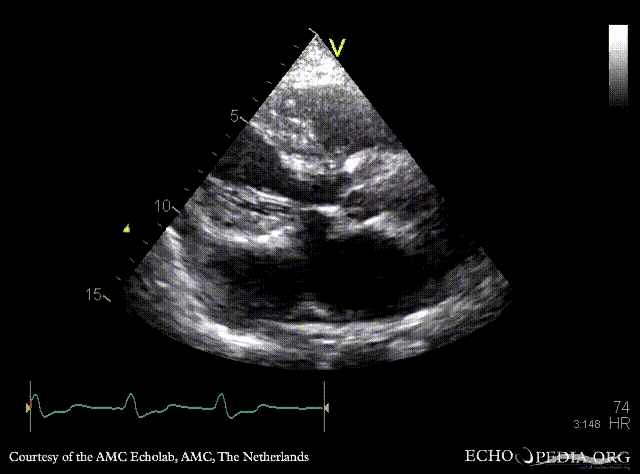

PLAX: dilated coronary sinus A4CH with Color Doppler: severe tricuspid regurgitation